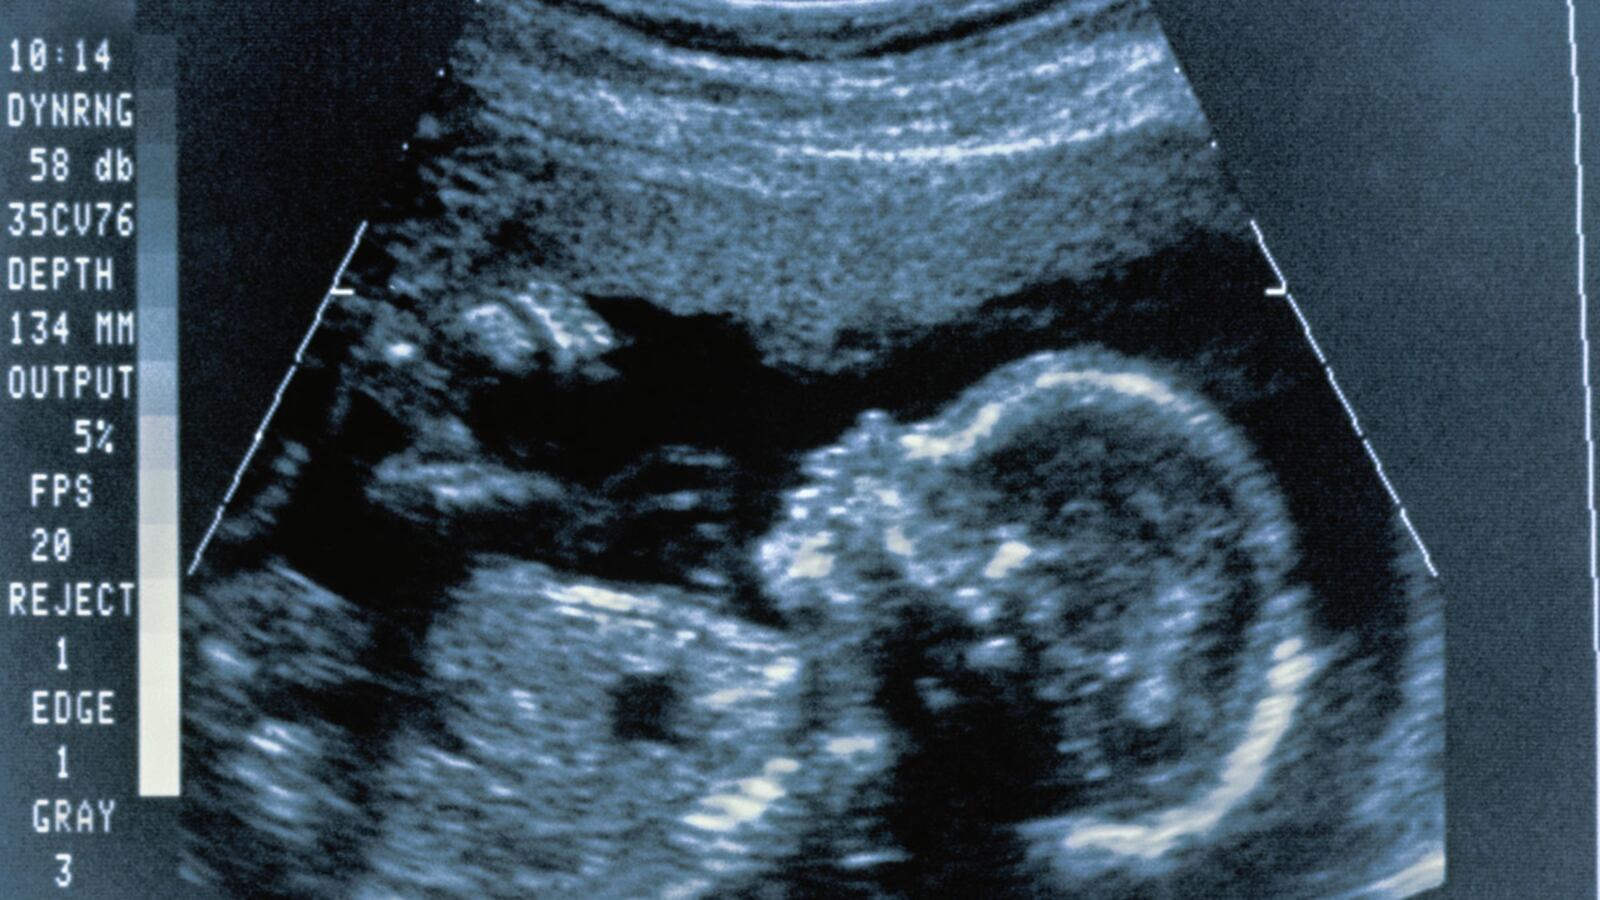

A federal judge in Texas struck down a provision of a Texas anti-abortion law that required a doctor to give a woman a sonogram before an abortion. U.S. District Judge Sam Sparks said in his ruling that the law violated the First Amendment rights of both doctors and patients. One of dozens of anti-abortion laws enacted across the country, Texas’s law had been set to take effect Thursday. Sparks’s ruling also struck down a requirement that allowed women to avoid seeing the sonogram images only if they signed a statement saying they were pregnant from sexual assault or incest, saying the state cannot force a woman to disclose information that she may not even wish to tell police.